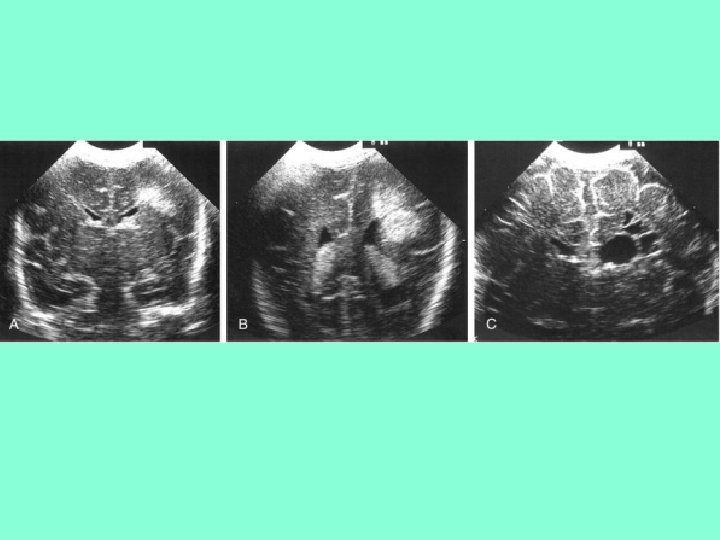

Классификация ПВЛМ From De. Vries L et al: The spectrum of leukomalacia using cranial ultrasound. Behav Brain Res 49: 1, 1992. • 1 степень – транзиторное перивентрикулярное увеличение эхоплотности в первые 7 дней жизни • 2 степени –локальные лобно-височные кисты • 3 степени - распространенные перивентрикулярные кисты • 4 степень – распространенные перивентрикулярные и субкортикальные кисты

• А – нормальный ребенок в 31 неделю ГВ • В и С - бивентрикулярные кисты